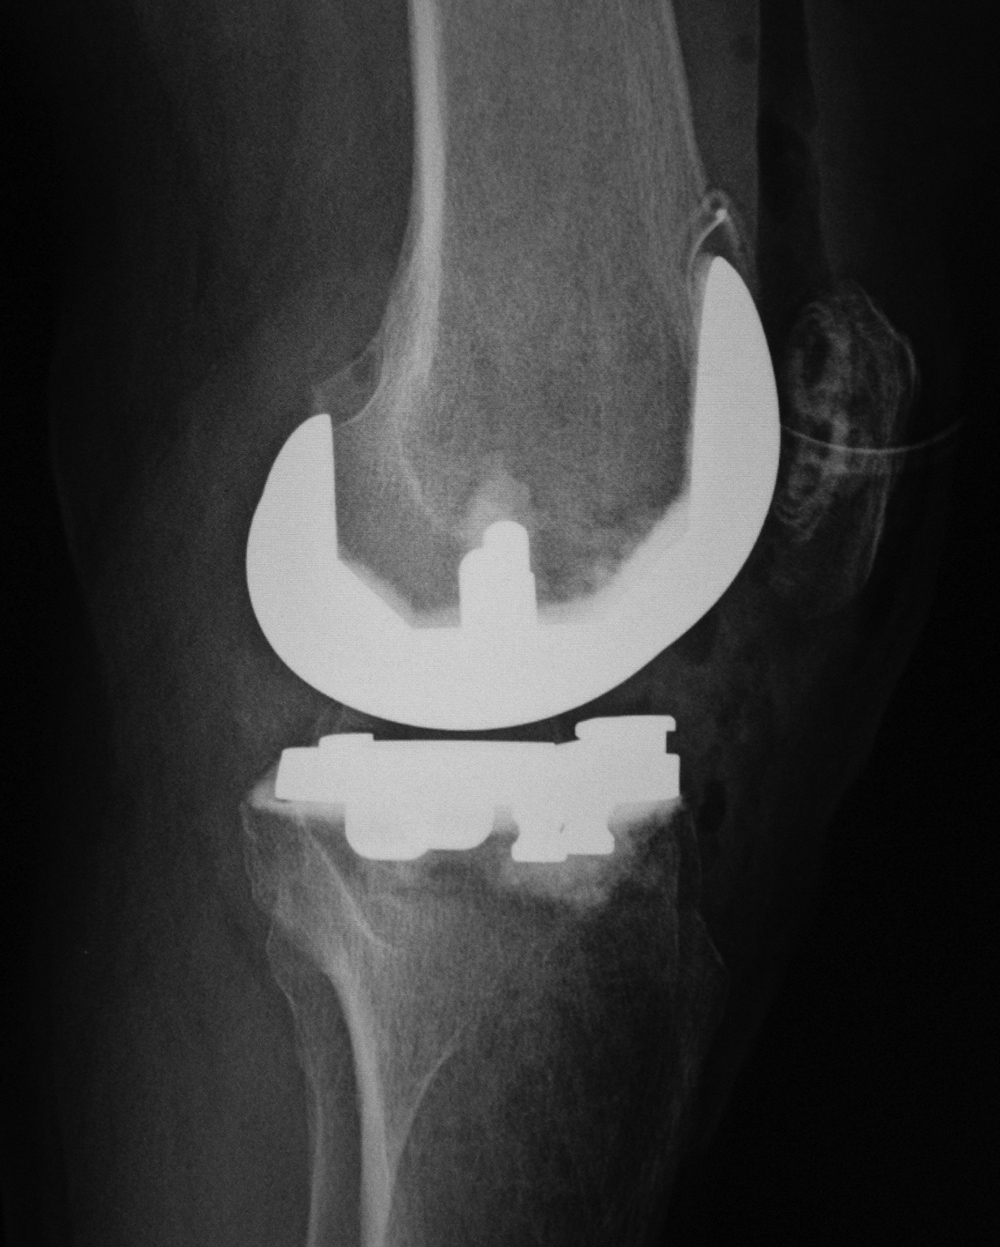

| 68 year-old woman treated for severe left knee osteoarthritis |

Note the large distal femoral box. There is a surgical drain in the suprapatellar space. |

| Biomet XPA Bicruciate Preserving total knee arthroplasty |

| 67 year-old woman. A surgical drain is present from recent surgery. From Taljanovic, 2005 |